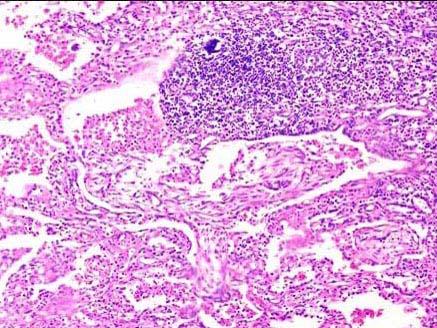

患者,1月前因高热,咳铁锈色痰伴呼吸困难入院。经治疗临床症状消失,但肺下叶实变灶不消失,手术切除,镜检如图所示,正确的诊断是 ( )A.吸入性肺炎...

问题 患者,1月前因高热,咳铁锈色痰伴呼吸困难入院。经治疗临床症状消失,但肺下叶实变灶不消失,手术切除,镜检如图所示,正确的诊断是 ( )

选项 A.吸入性肺炎 B.矽肺 C.肺肉质变 D.肺脓肿 E.肺癌

答案 C